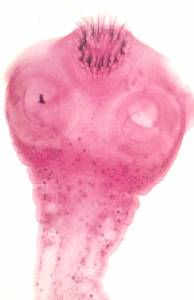

Фото. А, Б — Бычий цепень (Taeniarhynchus saginatus) на головке имеет четыре присоски и рудиментарный хоботок без крючьев — невооруженный цепень; в матке от срединного канала в обе стороны отходят 18-30 боковых ветвей с яйцами. В, Г — Свиной цепень (Taenia solium) на сколексе имеет четыре присоски и хоботок с двумя рядами крючьев — вооруженный цепень; в матке от срединного ствола в обе стороны отходят 7-10 боковых ветвей, т. е. в 3 раза меньше, чем в зрелом членике бычьего цепня.